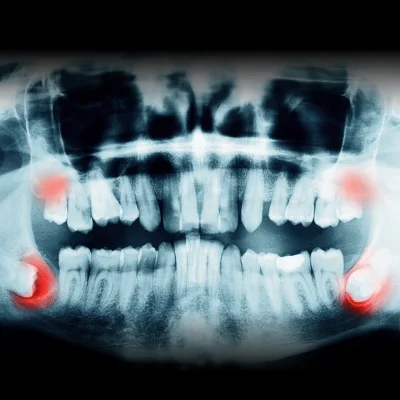

- การผ่าตัดฟันคุด

- ผู้ที่ต้องรักษาหลายขั้นตอนในครั้งเดียว เช่น การผ่าฟันคุดหลายซี่พร้อมกัน, การทำรากฟันเทียม